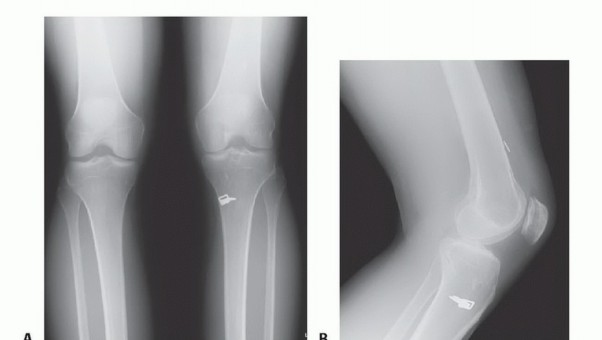

DEFINITION The posterolateral corner (PLC) of the knee is a complex area, both anatomically and functionally,…